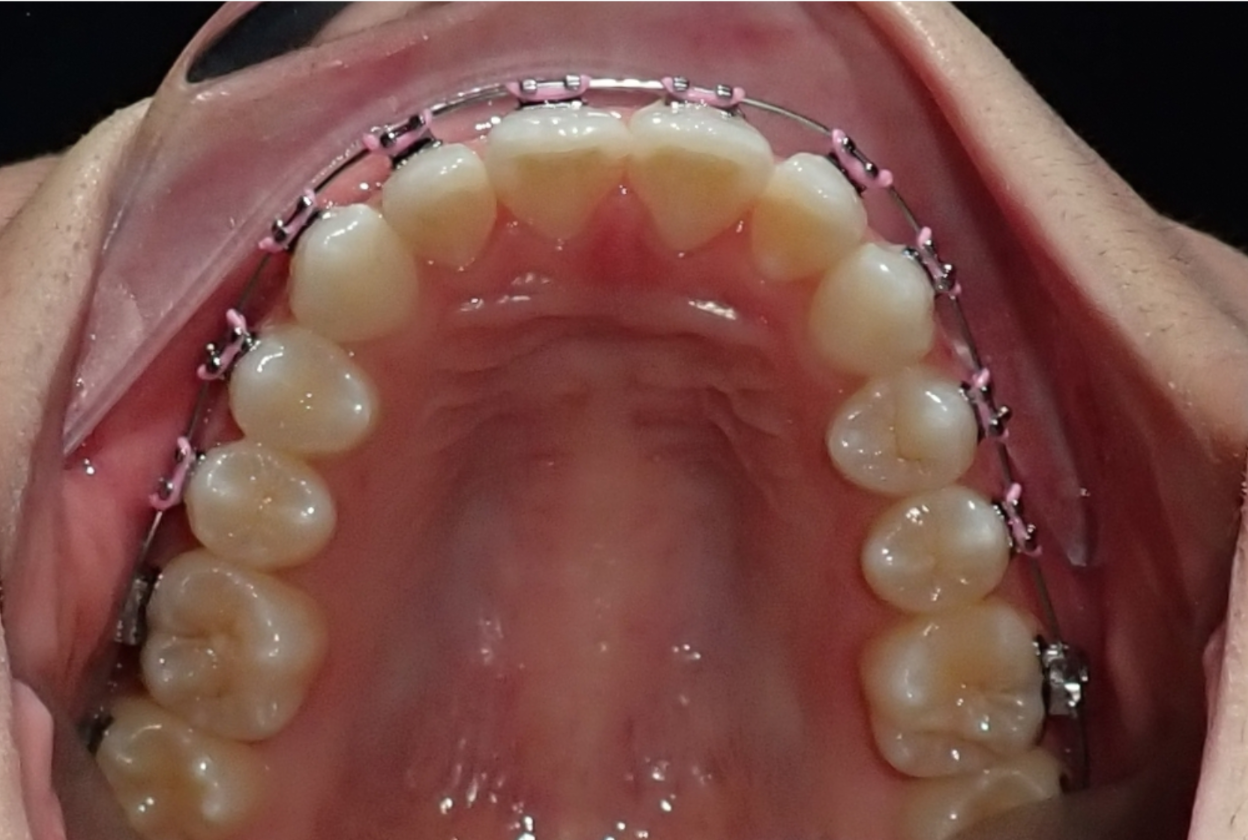

Expansor

Un expansor maxilar ensancha el maxilar superior para crear el espacio adecuado para los dientes y mejorar la forma en que encajan las mandíbulas superior e inferior. Puede ayudar a prevenir el apiñamiento, las mordidas cruzadas y futuros problemas ortodónticos. Esta intervención temprana favorece un crecimiento facial más saludable y contribuye a una sonrisa más equilibrada.

Inside of a person's mouth showing upper teeth with orthodontic braces with metal wires and pink elastic ties.